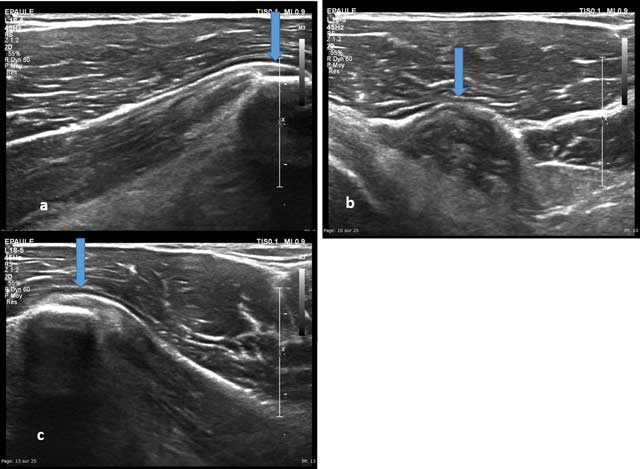

The ultrasound-guided exploration is performed in axial plane, arm in external rotation and then externally down to go on with the Biceps brachii and Coracobrachialis biceps muscles or internally to study the pectoralis minor (Figures 12–13).

Figure 12

Axial view of the coracoid process with enthesis of the short head of the biceps brachii (a and b) and the coracobrachialis (c).